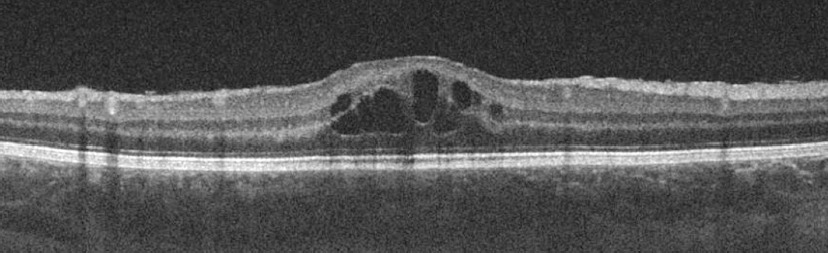

Approximately three weeks after tumor resection, OCT revealed macular edema in the right eye (Figure 5). A steroid (methylprednisolone acetate, Depo-Medrol) was administered via injection under Tenon’s capsule. Two months later, the patient developed left eye uveitis, evidenced by inflammatory cells in the anterior chamber of the left eye.